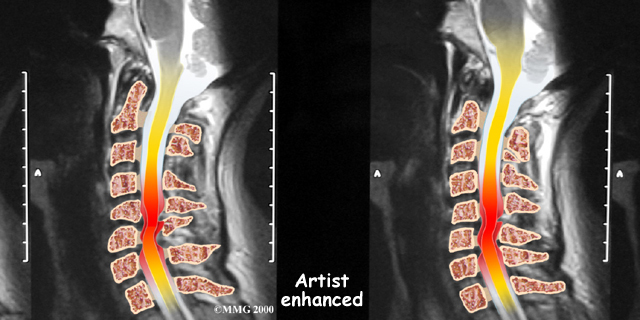

If more information is needed, a magnetic resonance imaging (MRI) scan may be ordered. The MRI machine uses magnetic waves rather than X-rays to show the soft tissues of the body. This test gives a clear picture of the spinal cord and can show where it is being squeezed. An MRI machine creates pictures that look like slices of the area your healthcare professional is interested in. This test does not require any special dye or a needle.

The bony spinal canal normally has more than enough room for the spinal cord. Typically, the canal is just less than ¾ of an inch, or 17-18 millimeters around, which is less than the size of a small bottle cap. Spinal stenosis occurs when the canal narrows to around half an inch, or 13 millimeters or less. When the size drops even further, severe symptoms of myelopathy occur. The symptoms of myelopathy result from the actual pressure against the spinal cord itself as well as the reduced blood supply in the spinal cord as a result of the pressure.